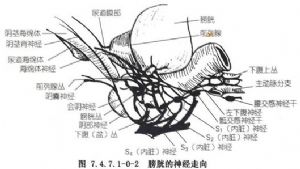

控制排尿的神經很複雜,包括兩個神經中樞和3組神經,即脊髓反射中樞、脊上反射中樞和交感神經、副交感神經及體神經。膀胱和尿道的粘膜與肌肉的傳入纖維經感覺支進入脊髓中樞。副交感神經進入S2~S4脊髓,運動支經盆神經及盆神經叢而達膀胱及後尿道平滑肌。交感神經進入T11~L2脊髓,運動支經椎旁交感神經節、主動脈神經叢、骶前神經叢分爲左右腹下神經而達膀胱三角區、頸部、後尿道、前列腺及精囊。體神經進入S2~S4脊髓,運動支經陰部神經分佈至尿道外括約肌、肛提肌、坐骨海綿體肌、球海綿體肌及肛門外括約肌。排尿的生理過程主要受副交感神經控制。脊上反射中樞包括大腦皮質、下丘腦和腦幹等。大腦和下丘腦對排尿主要起抑制作用,而腦幹主要使膀胱在排尿時產生持久而有效的收縮。當排尿失去脊上反射中樞的支配時,骶髓反射中樞即獨立地調節排尿功能(圖7.4.7.1-0-1,7.4.7.1-0-2)。